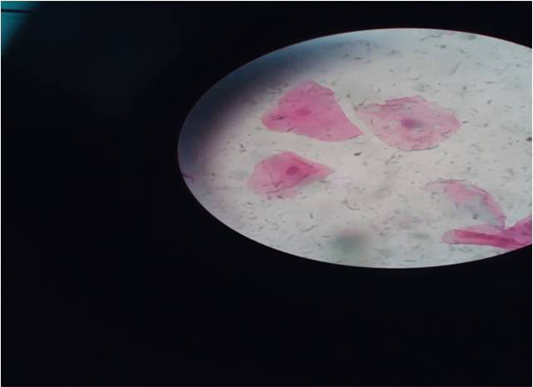

Figure 2

Intermediate cells under microscope